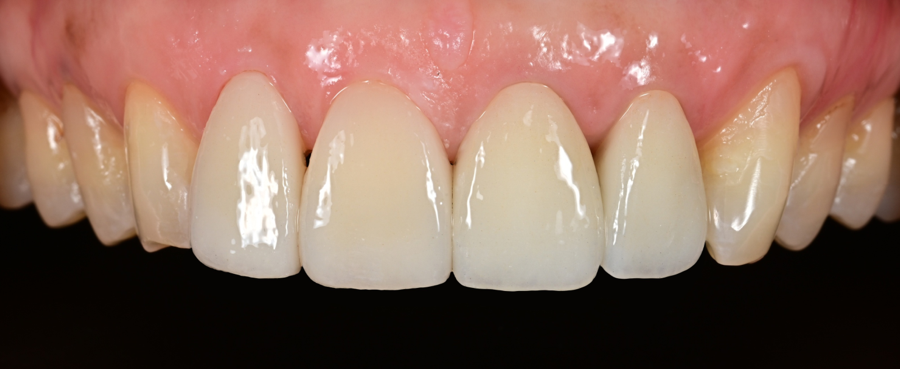

After the adjustments were completed,

the patient said,

“Most of the bothersome feeling when chewing is gone.”

“It no longer feels as sensitive as before, even when I drink cold water.”

In particular, the habit of chewing only on one side during meals decreased,

and as the patient became able to use both sides evenly,

the overall feeling of use became much more comfortable.